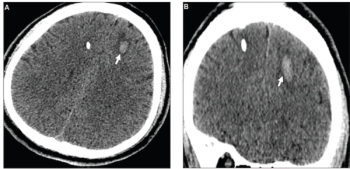

Adjunctive AI showed no difference in accuracy than unassisted radiologists for intracranial hemorrhage (ICH) detection and had a slightly longer mean report turnaround time for ICH-positive cases, according to newly published prospective research.